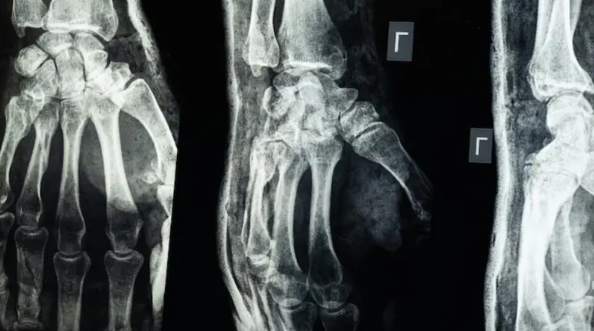

أعلن فريق بحثي في مقاطعة تشيجيانغ شرق الصين عن ابتكار طبي جديد يتمثل في “غراء عظمي” قادر على معالجة الكسور وتركيب الشظايا العظمية خلال ثلاث دقائق فقط، في خطوة وُصفت بأنها اختراق علمي في عالم جراحة العظام، بحسب ما نقل موقع “إن دي تي في” NDTV.

وأكدت الاختبارات المعملية أن Bone-02 نجح في تحقيق نتائج جيدة من حيث السلامة والفعالية. وفي إحدى التجارب، أُجريت العملية في أقل من 180 ثانية (ثلاث دقائق)، بينما كانت طرق العلاج التقليدية تتطلب وقتاً طويلاً لزرع صفائح فولاذية ومسامير.

وبحسب الاختبارات المعملية، تمكن الغراء من تحقيق قوة ربط تفوق 400 رطل، وقوة قص تبلغ نحو 0.5 ميغاباسكال، وقوة ضغط تقارب 10 ميغاباسكال. كما أظهرت التجارب على أكثر من 150 مريضاً نتائج ناجحة، ما يعزز احتمالية أن يصبح بديلاً للزراعات المعدنية التقليدية التي تُستخدم في تثبيت العظام. كما يقول العلماء إنه قد يقلل أيضًا من مخاطر العدوى.